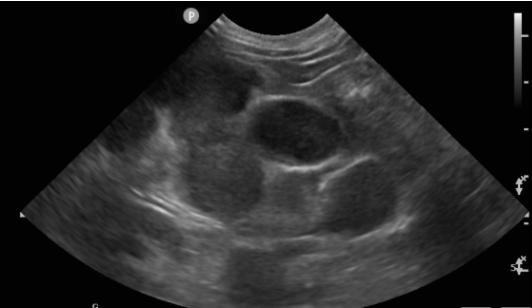

貓 淋巴癌 胸水 胸腔前縱膈腔腫瘤 腹腔淋巴結腫大 化療 不是感冒 首頁 病例分享 腫瘤科 貓 淋巴癌 胸水 胸腔前縱膈腔腫瘤 腹腔淋巴結腫大 化療 不是感冒 1歲已絕育母貓,就診前一周精神食慾下降、咳嗽,在他院診斷感冒治療無效而就醫。 經急診醫師檢查發現有嚴重胸水、前縱膈團塊、腹腔淋巴結腫大。 排除心臟病、白血病等等鑑別診斷後採樣確診為貓咪的淋巴癌。 雖然淋巴癌的治癒率非常低,但對化療有良好反應的機率很高,於是後續開始化療計畫。 影像檢查結果 嚴重胸水 抽完胸水後發現前縱膈腔團塊. 腹腔內淋巴結多發腫大 病理切片: 箭頭所指處為有絲分裂中的淋巴癌細胞